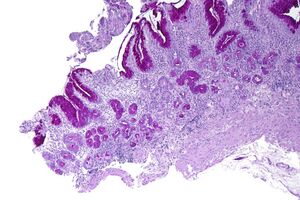

| Micrograph showing nodular enterochromaffin-like cell hyperplasia, as demonstrated with chromogranin A immunostaining, in the body of the stomach. Parietal cells are not readily apparent. These changes are in keeping with autoimmune metaplastic atrophic gastritis, a histologic correlate of vitamin B12 deficiency anemia. | |

PA may be considered as an end stage of autoimmune atrophic gastritis, a disease characterised by stomach atrophy and the presence of antibodies to parietal cells and intrinsic factor.[38][39] Autoimmune atrophic gastritis, is localised to the body of the stomach, where parietal cells are located.[36] Antibodies to intrinsic factor and parietal cells cause the destruction of the oxyntic gastric mucosa, in which the parietal cells are located, leading to the subsequent loss of intrinsic factor synthesis. Without intrinsic factor, the ileum can no longer absorb the B12.[40] Atrophic gastritis is often a precursor to gastric cancer.[39]